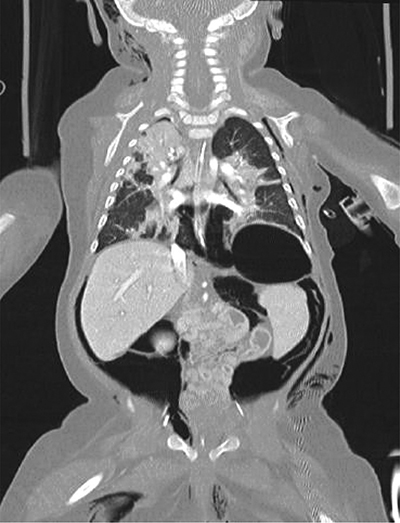

A whole body low-dose computed tomography (CT) scanner showed a tension pneumothorax leading to decreased cardiac output. It also showed extensive deep tissue emphysema (latero-thoracic and right-cranial), pneumomediastinum, pneumopericardium, and important retroperitoneal free air without pneumoperitoneum (Figures 4 and 5).

Figure 4

Whole body low-dose CT scanner.

Latero-thoracic and right-cranial subcutaneous emphysema along with massive free air (e.g., pneumomediastinum and pneumopericardium).

Further, it showed abdominopelvic ascites, periportal, and perivascular edema. There was cleavage of all abdominal layers produced by the free air (Figure 6).

Cleavage of all abdominal layers produced by the free air.